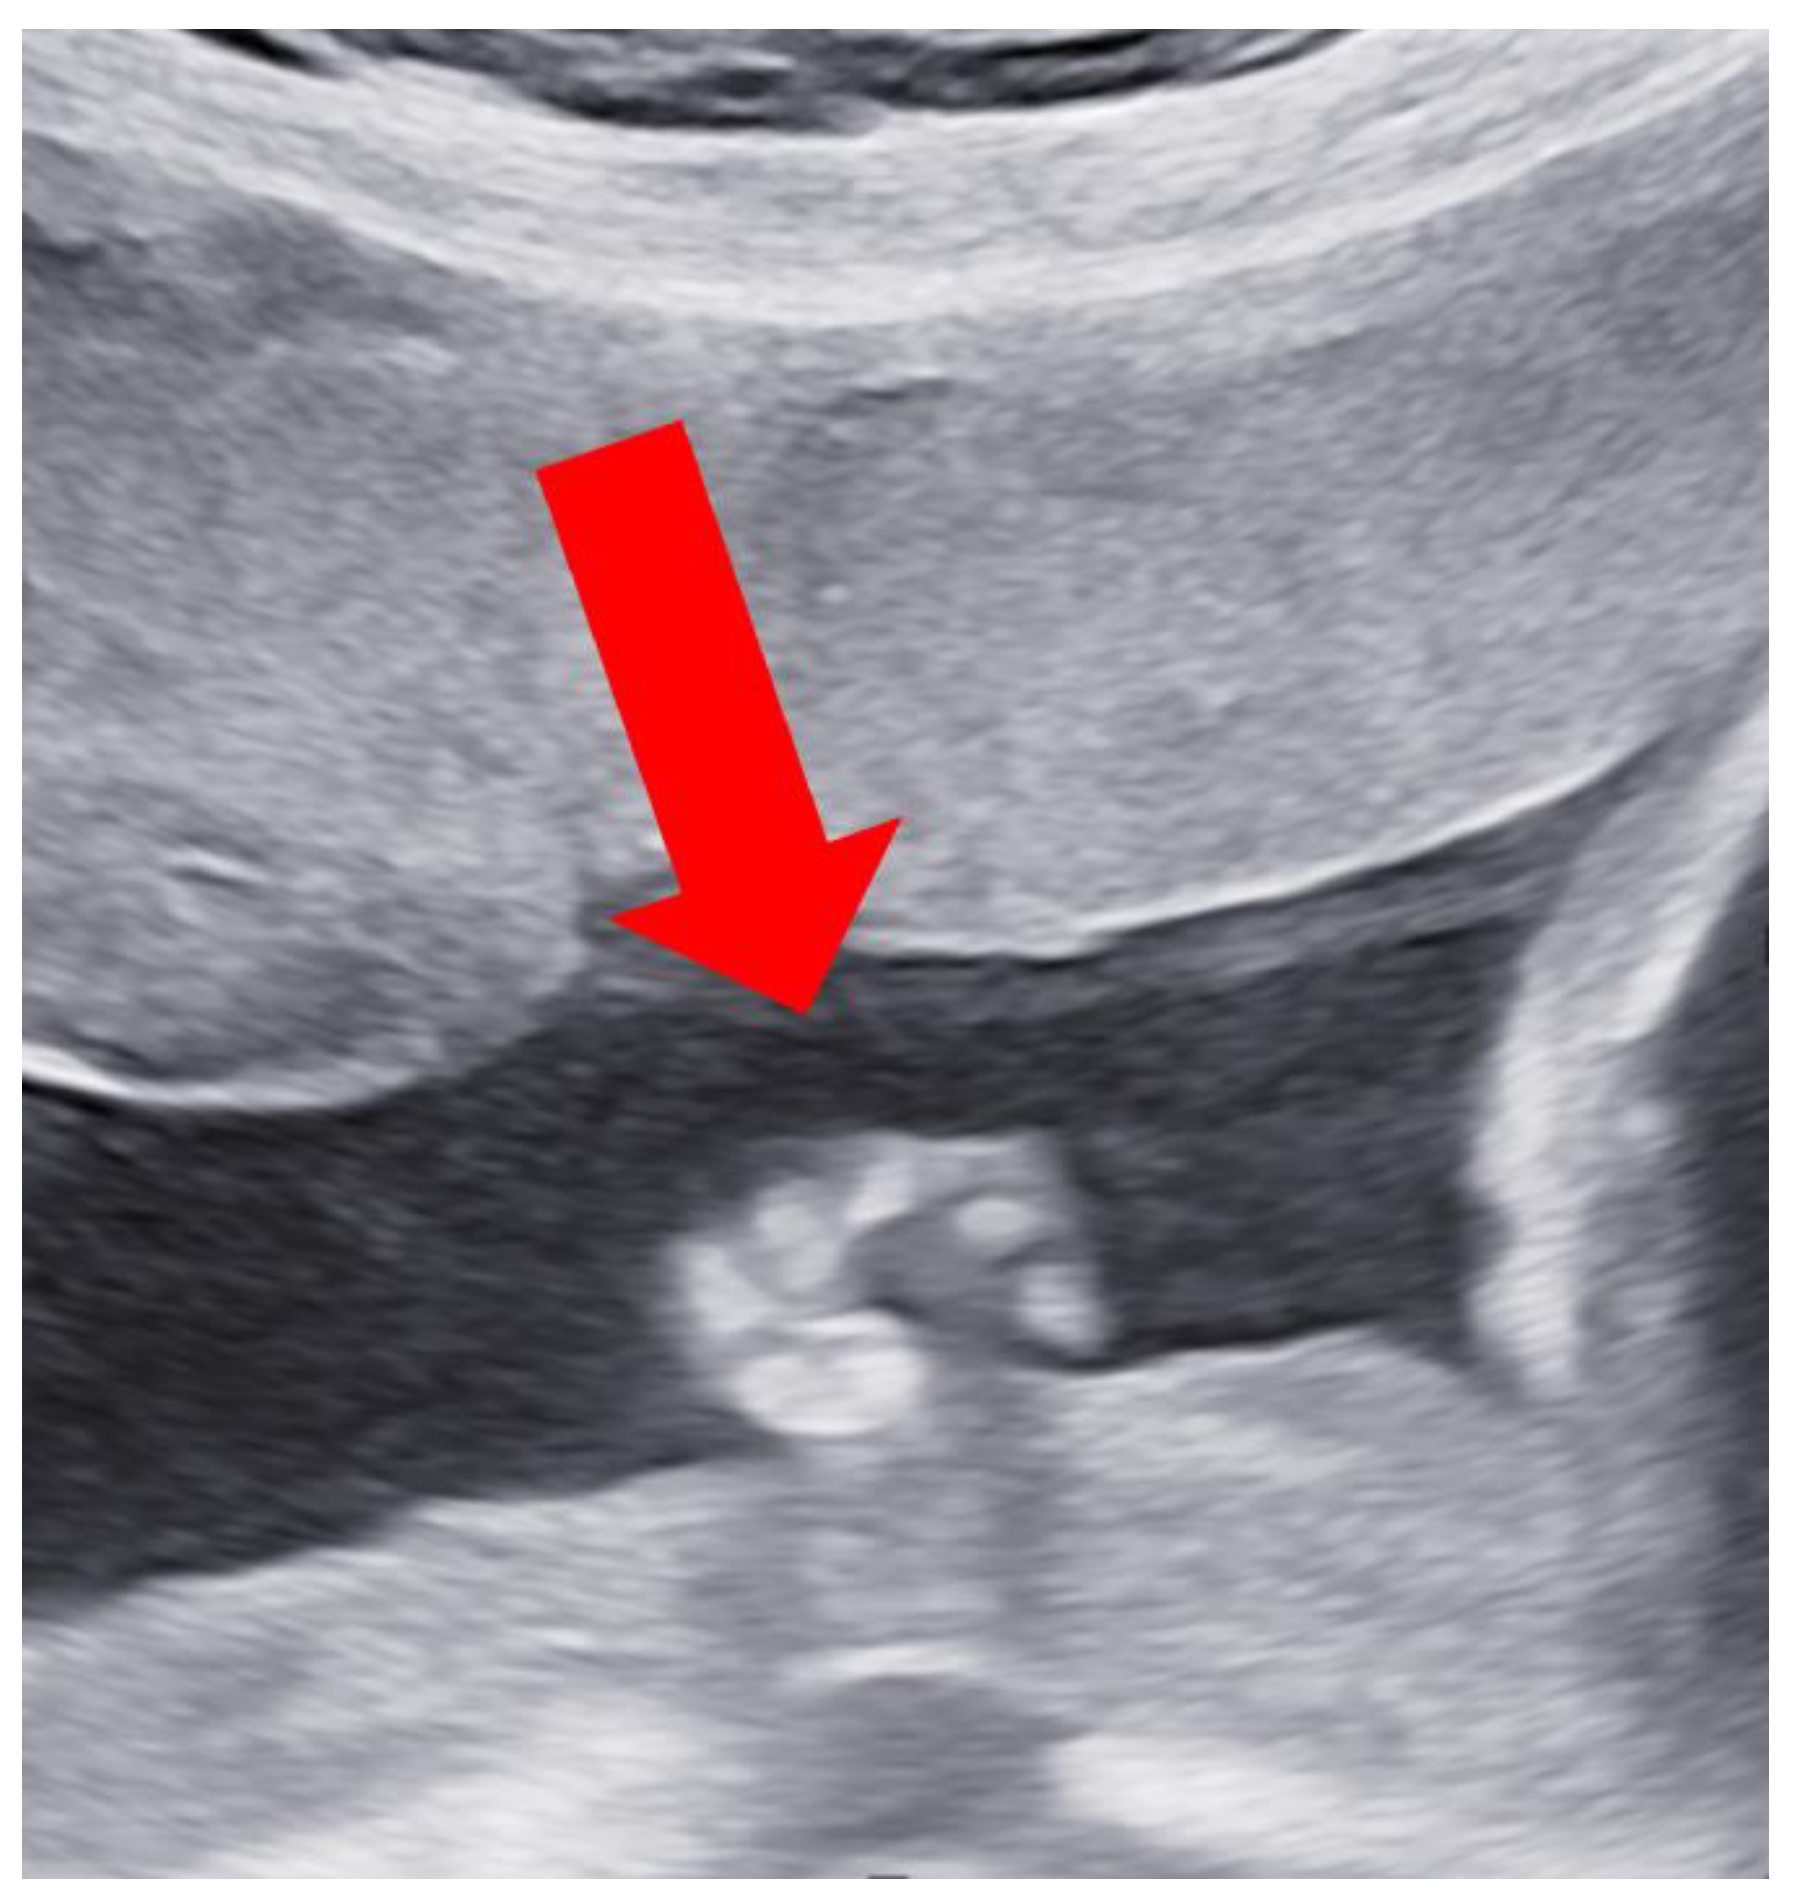

Case Report

4. Discussion and Conclusions